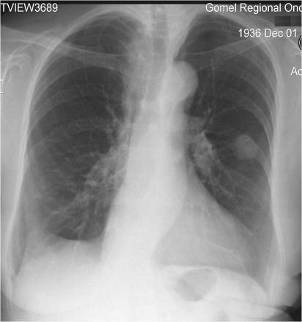

К-Т картина периферического рака легкого характеризуется такими же признаками, как и в традиционной рентгенодиагностике: образование неправильной округлой формы с нечеткими неровными контурами. Эти отличия периферического рака от доброкачественных образований и метастазов проявляются в виде широкой (более 3-4 мм) зоны увеличения плотности вокруг опухоли (от - 550 до - 250 ед. Н), а плотность самой злокачественной опухоли расположена в диапазоне от +30 до + 60 ед.Н. КТ позволяет выявить возможный распад опухоли с образованием полости при пересмотре срезов на более низком "окне" (Приложение А рисунок 5). При помощи КТ удается обнаружить и явления регионарного лимфангита в виде "дорожки" между корнем легкого и опухолью. В отличие от сосудов "дорожка" уменьшается по ширине от образования к корню легкого.

К-Т исследование позволяет изучить взаимоотношение между периферическим раком и органами средостения, а также элементами грудной стенки.

Прорастание опухоли проявляется, в первую очередь, в том, что:

а) опухоль локализуется как в легком, так и в средостении с вовлечением в процесс крупных сосудистых структур;

б) между опухолью, средостением и плеврой отсутствует жировая клетчатка;

в) имеется наличие жидкости в полости перикарда и утолщение его стенки;

г) при непосредственной близости опухоли к плевре последняя утолщена и подтянута к узлу.

Увеличенные свыше 10 мм лимфоузлы, что указывает на их метастазирование, особенно в области бифуркации трахеи и легочных корней, имеют тенденцию к слиянию. В то же время в неувеличенных лимфоузлах в 20-25% случаев выявляются скрытые метастазы рака легкого.

Исходя из этих данных, степени операбельности рака легкого при КТ исследовании определяют по таким признакам: вовлечение в опухолевый процесс смежных элементов средостения (перикарда, верхней полой вены), а также плевры и других структур грудной стенки (Приложение А рисунок 6). Метастатическое поражение лимфоузлов средостения.

Широкие возможности в этом плане открывает компьютерная томография. Этот метод позволяет оценивать вовлечение в опухолевый процесс главного бронха, легочных сосудов и структур средостения. Выявляемая при компьютерной томографии ограниченная инвазия перикарда, медиастинальной плевры и пограничной жировой ткани, легочных вен и диафрагмальных нервов свидетельствует о возможности радикальной операции. Распространение же опухолевого процесса на сердце, крупные сосуды, пищевод, трахею и тела позвонков является противопоказанием к операции. Компьютерная томография позволяет оценить состояние лимфатических узлов средостения, что является важным и для определения стадии процесса, оценки операбельности и прогноза заболевания. По мнению большинства авторов, при размерах лимфатического узла менее 7 мм, метастазы в них, как правило, отсутствуют [2].